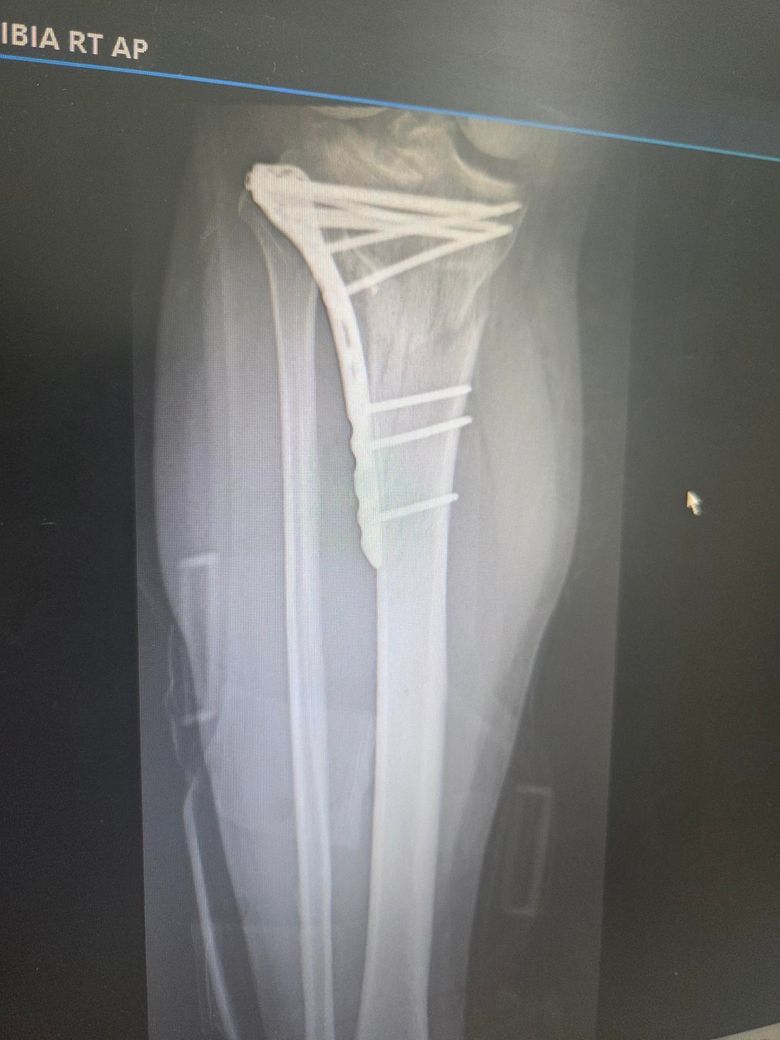

제목 그대로입니다. 6월말에 오른발 정강이뼈 분쇄골절상을

입어서 병원에 잇는데 수술도 잘되고 이제 진통제 안맞아도 될

정도로 좋아졌는데 뼈가 너무 심하게 부서져서 뼈가 붙는데

데까지 시간이 오래 걸린다네요 ㅠㅠㅠ

• 1번 째 사진